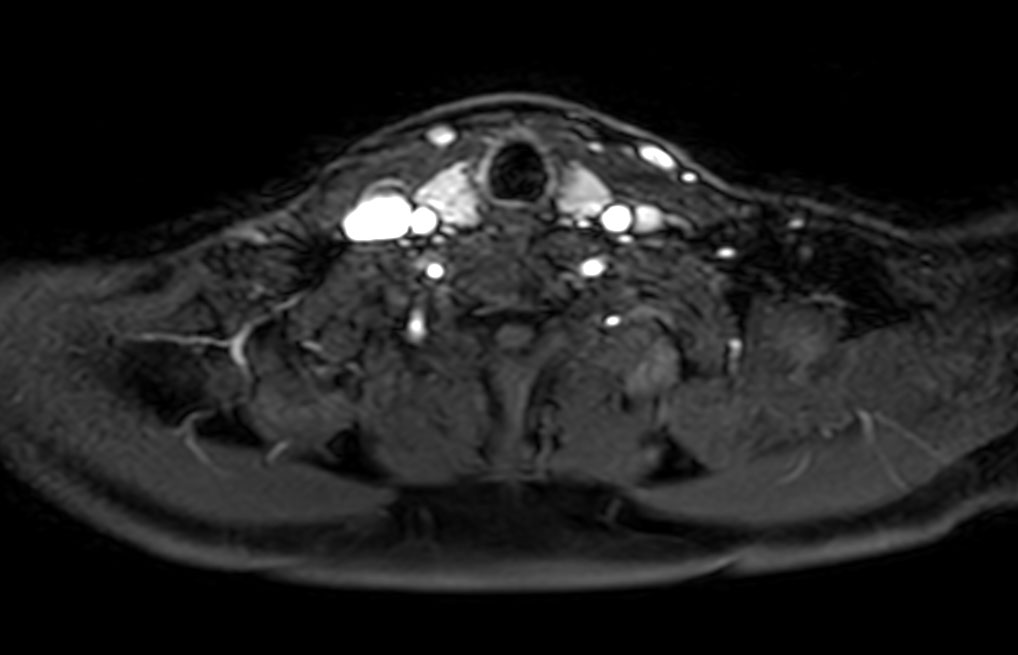

Axial T2w mDIXON XD TSE (In Phase)

Axial T2w mDIXON XD TSE (Water only)